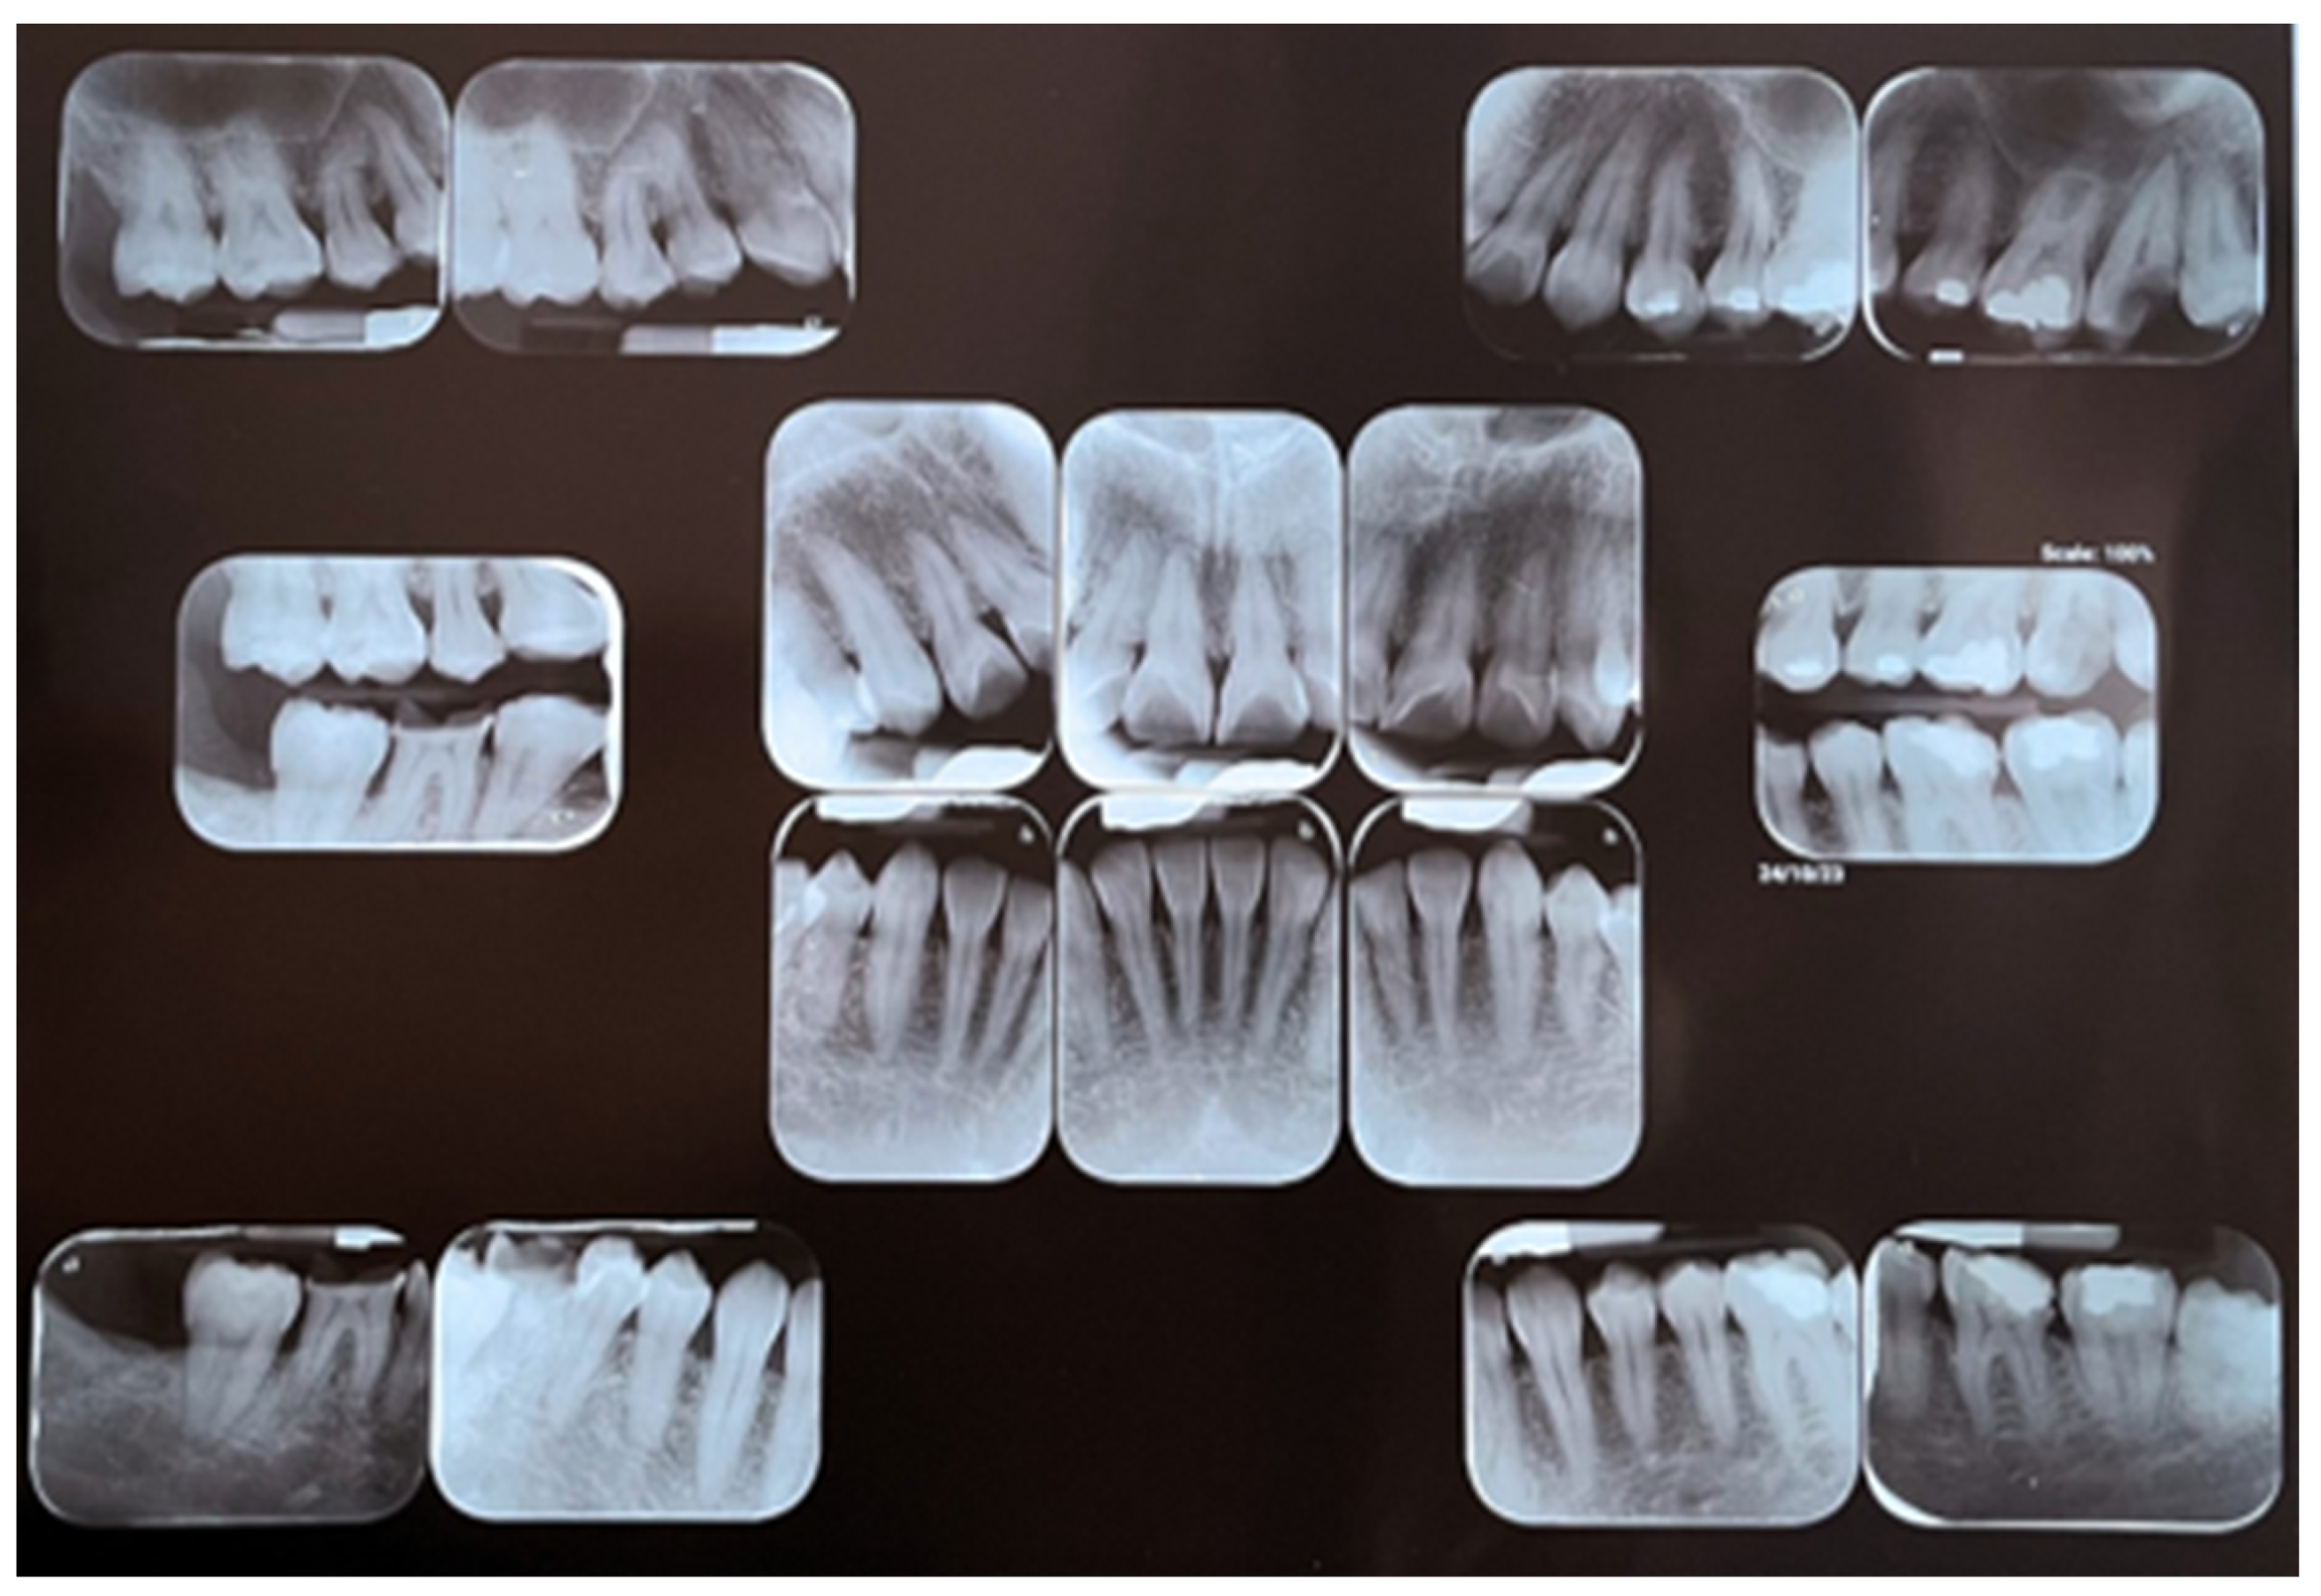

2.1. Clinical Findings